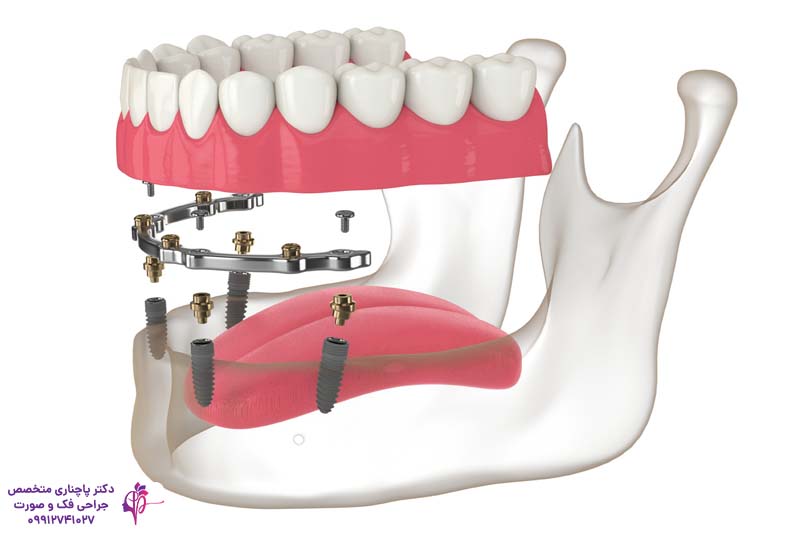

- اوردنچر با بار فلزی یا bar-retained

در آن یک میله فلزی روی ایمپلنتها قرار میگیرد و پروتز با کلیپس به آن متصل میشود. این مدلها ثبات خوبی دارند و راحت نیرو را توزیع میکنند ولی نصب آنها راحت نیست و در نتیجه تمیز کردن آنها سختتر میشود.